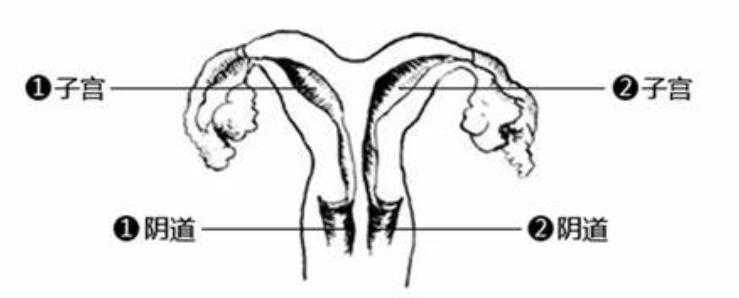

纵隔子宫属于先天性子宫发育畸形,通常对性生活无直接影响。但若伴有阴道纵隔,同房时可能会产生疼痛感。在辅助生殖术前检查中,若发现纵隔导致了反复流产或不孕,则需进行宫腔镜手术。若妇科阴道镜显示阴道同样存在发育畸形,可配合进行阴道整形手术,以改善生活质量及后续受孕条件。